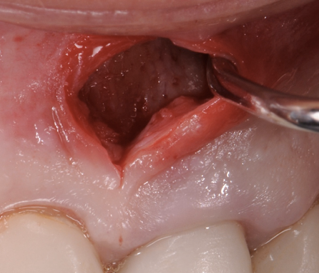

The patient had a congenitally missing upper right lateral incisor. Orthodontic treatment was performed to create the necessary space for a dental implant. Unfortunately, the implant failed, and so did several subsequent attempts to bone graft. These failures resulted in a visible smile deformity, that got worse after each failed procedure.

After the 3rd bone graft failed, the patient sought second opinions. She was a college sophomore at the time. Using a combination of interdisciplinary therapies, including S.M.A.R.T. minimally invasive bone grafting, Dr. Ernesto Lee was able to tridimensionally reconstruct this severe defect and place implants to restore the patient’s smile. The S.M.A.R.T. bone graft was also extended to treat adjacent teeth with thin/dehisced bone.